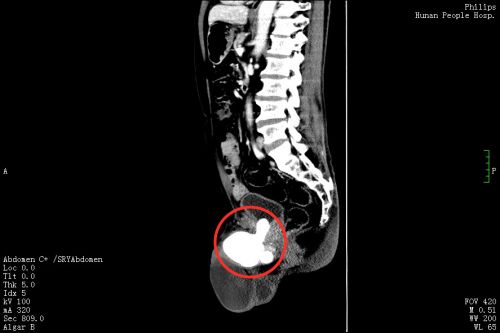

3月11日,刘先生在家人陪同下来到捷克论坛 泌尿外科门诊就诊,郭琼副主任医师接诊后,仔细询问病史并进行体格检查后发现,老人的左侧阴囊肿大,内有一个卵圆形的囊性肿块,符合“左侧睾丸鞘膜积液”的诊断。然而让医师惊讶的是,患者的绝大部分阴茎内都充满了坚硬的结节,压痛十分明显,高度怀疑是尿道结石。果然,泌尿系CT 检查发现,其膀胱尿道口和尿道内有一个鹅蛋大的结石,这正是导致老人持续会阴剧痛、尿频、尿急、排尿困难的罪魁祸首,随即将他收入泌尿三科病房。

郭琼副主任医师团队综合评估患者病情后,为他制定了“一石二鸟”的手术方案,一次手术同时解决尿道结石和睾丸鞘膜积液两个问题。322日,手术团队在全麻下为刘先生施行“左侧鞘膜翻转、尿道切开取石、尿道修补、膀胱镜检查、膀胱造瘘术”。在患者的后尿道及部分前尿道取出约10×8.1×4.5cm3大小重达256g,形态不规则、质地坚硬的结石。手术过程十分顺利,术中几乎无出血。